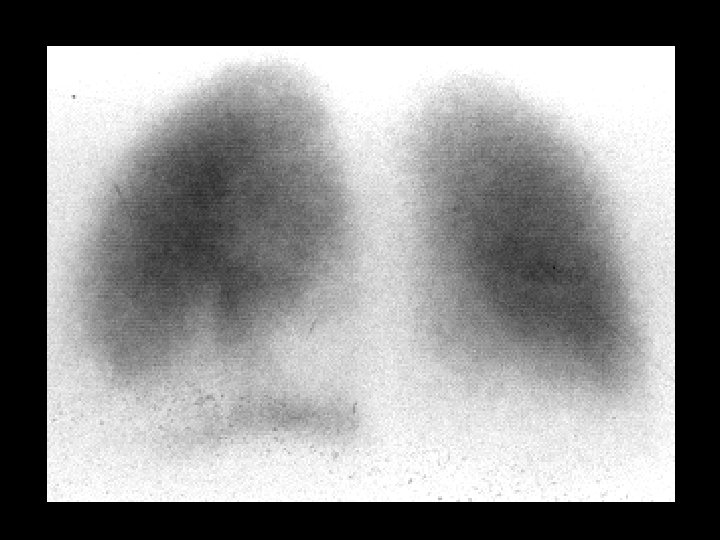

Pulmonary gallium uptake due to Chemo. Rx • • Ga-67 citrate, 5 -10 m. Ci, i. v. Diffuse pulmonary uptake, normal bone, lacrimal glands, liver, and spleen uptake correlate with normal CXR ddx: – pneumonia (PCP in AIDS) – lymphoma – vasculitis